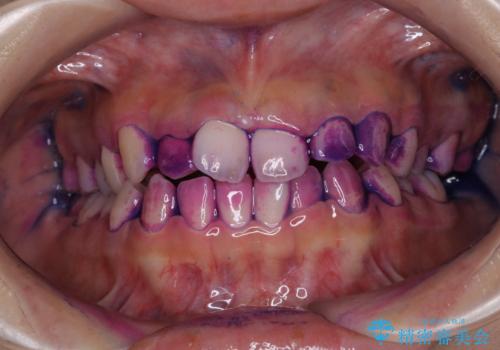

染め出し液を使ってプラークを染め出すことにより、普段の歯みがきで磨き残している場所を目で確かめることができます。

日々の歯磨きを上達するには、まずどこが磨けていないか認識することが大切です。

- しばらく歯科でのメンテナンスを受けていないため、歯磨きのチェックとクリーニング希望とのことで来院されました。

染め出しをしてのブラッシング指導とPMTCを行いました。